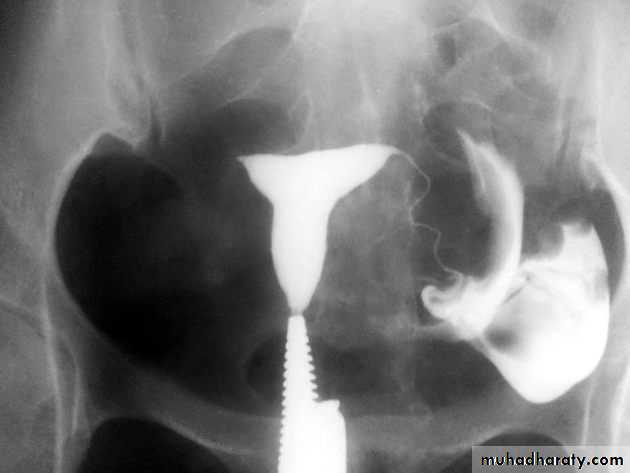

HSG showing a normal uterus and blocked tubes No "spill" of dye is seen at the ends of the tubes Both tubes are slightly dilated and fluid filled - hydrosalpinxHSG : fibroid is pushing in to the uterus cavity